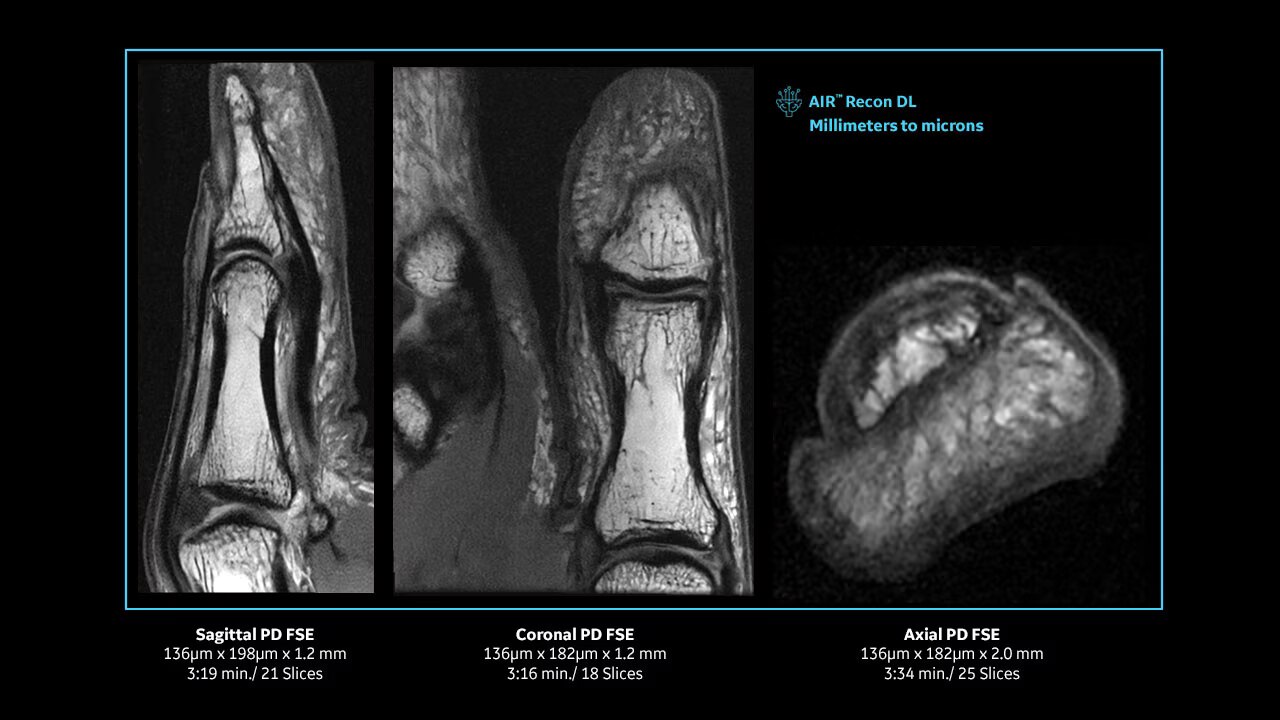

Achieve pin-sharp image quality with pioneering AIR™ Recon DL AI technology.

With access to the latest advanced AI technology, you can scan all anatomies and achieve pin-sharp images. Our pioneering deep learning-based reconstruction algorithm AIR Recon DL accelerates scan time and puts patients at ease.